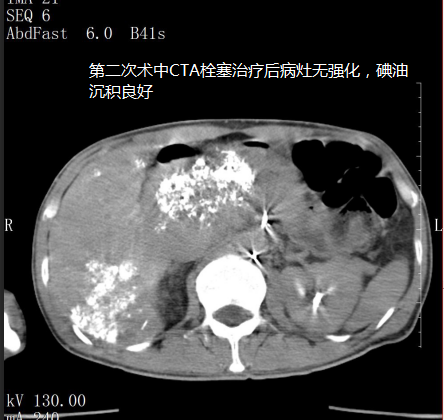

苏先生进行第二次微血管介入治疗后明显感受自己的身体变得轻盈,可以进行简单的饮食,精神状态变好了。

在5月3日苏先生的肝指标检查中甲胎蛋白降为6671IU/ml(参考值0~5.8),随后王峰医生实时跟进苏先生病情为他制定后续的治疗方案,为他开对应的药物治疗;5月14日苏先生的肝指标检查中甲胎蛋白降为18.70U/ml(参考值0~5.8)。

5月18日是苏先生进行第三次微血管介入治疗,治疗后苏先生完全可以自理,饮食恢复正常,面色也慢慢红润起来,肿瘤从原来的16公分缩小至10公分,甲胎蛋白逐渐趋向正常,看到这样的结果也让医生们深感很欣慰,连苏先生也意想不到,前段时间自己还是生命濒危的癌症患者现在却可以像正常人一样生活。他觉得这是上天给他最大的惊喜。